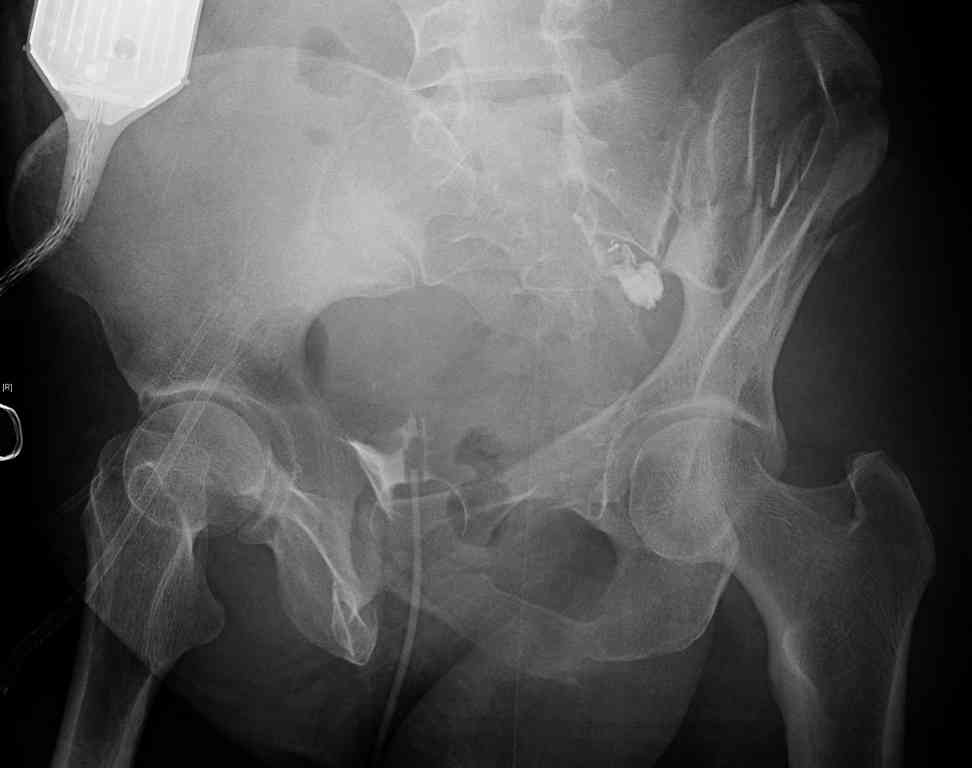

comminuted crescent fx

40 ish female ejected from car. Unstable, DPL negative, went to angio and had her pelvic bleeds embolized after many units of blood. GCS 6, floating elbow, clavicle, bothbones, etc.

My standard approach to this pelvis would be posterior, reduce/lag/plate thecrest, reduce/plate the caudal extent on the posterior crest and 1-2 lags back to front. In this case, the crest comminution seems to make plating all the way to the ASIS useless, as the plate would be on free floating fragments. Would plating the posterior extent of the fracture to secure the reduction at the SI joint and 2 screws back to front be sufficient fixation? Would anyone do a perc reduction and perc back to front screws, and would that be sufficient if the SI joint could be reduced (although I don't see how this could be accurately reduced closed). Would an ilioninguinal with a pelvic brim plate and posterior column screws be a better approach, although reducing the SI would be more indirect and less accurate?

It's a comminuted iliac fracture involving the GS notch and all that

implies...use the lateral interval of an ilioinguinal, sequentially reduce,

and fix...if you want to, you can attach the dominant unstable fragment to

both the stable posterior iliac fragment and also to the anterolateral portion of the sacrum using plates...if you choose to anchor to both, the implants get congested on the iliac side of the SI joint so be precise with contouring and such applications...perhaps and based on the images shown, an iliosacral screw would only augment the construct if applied to the second sacral segment (but this is difficult to assess on the images shown). The crest components can be held securely with screws and/or peripheral plating.